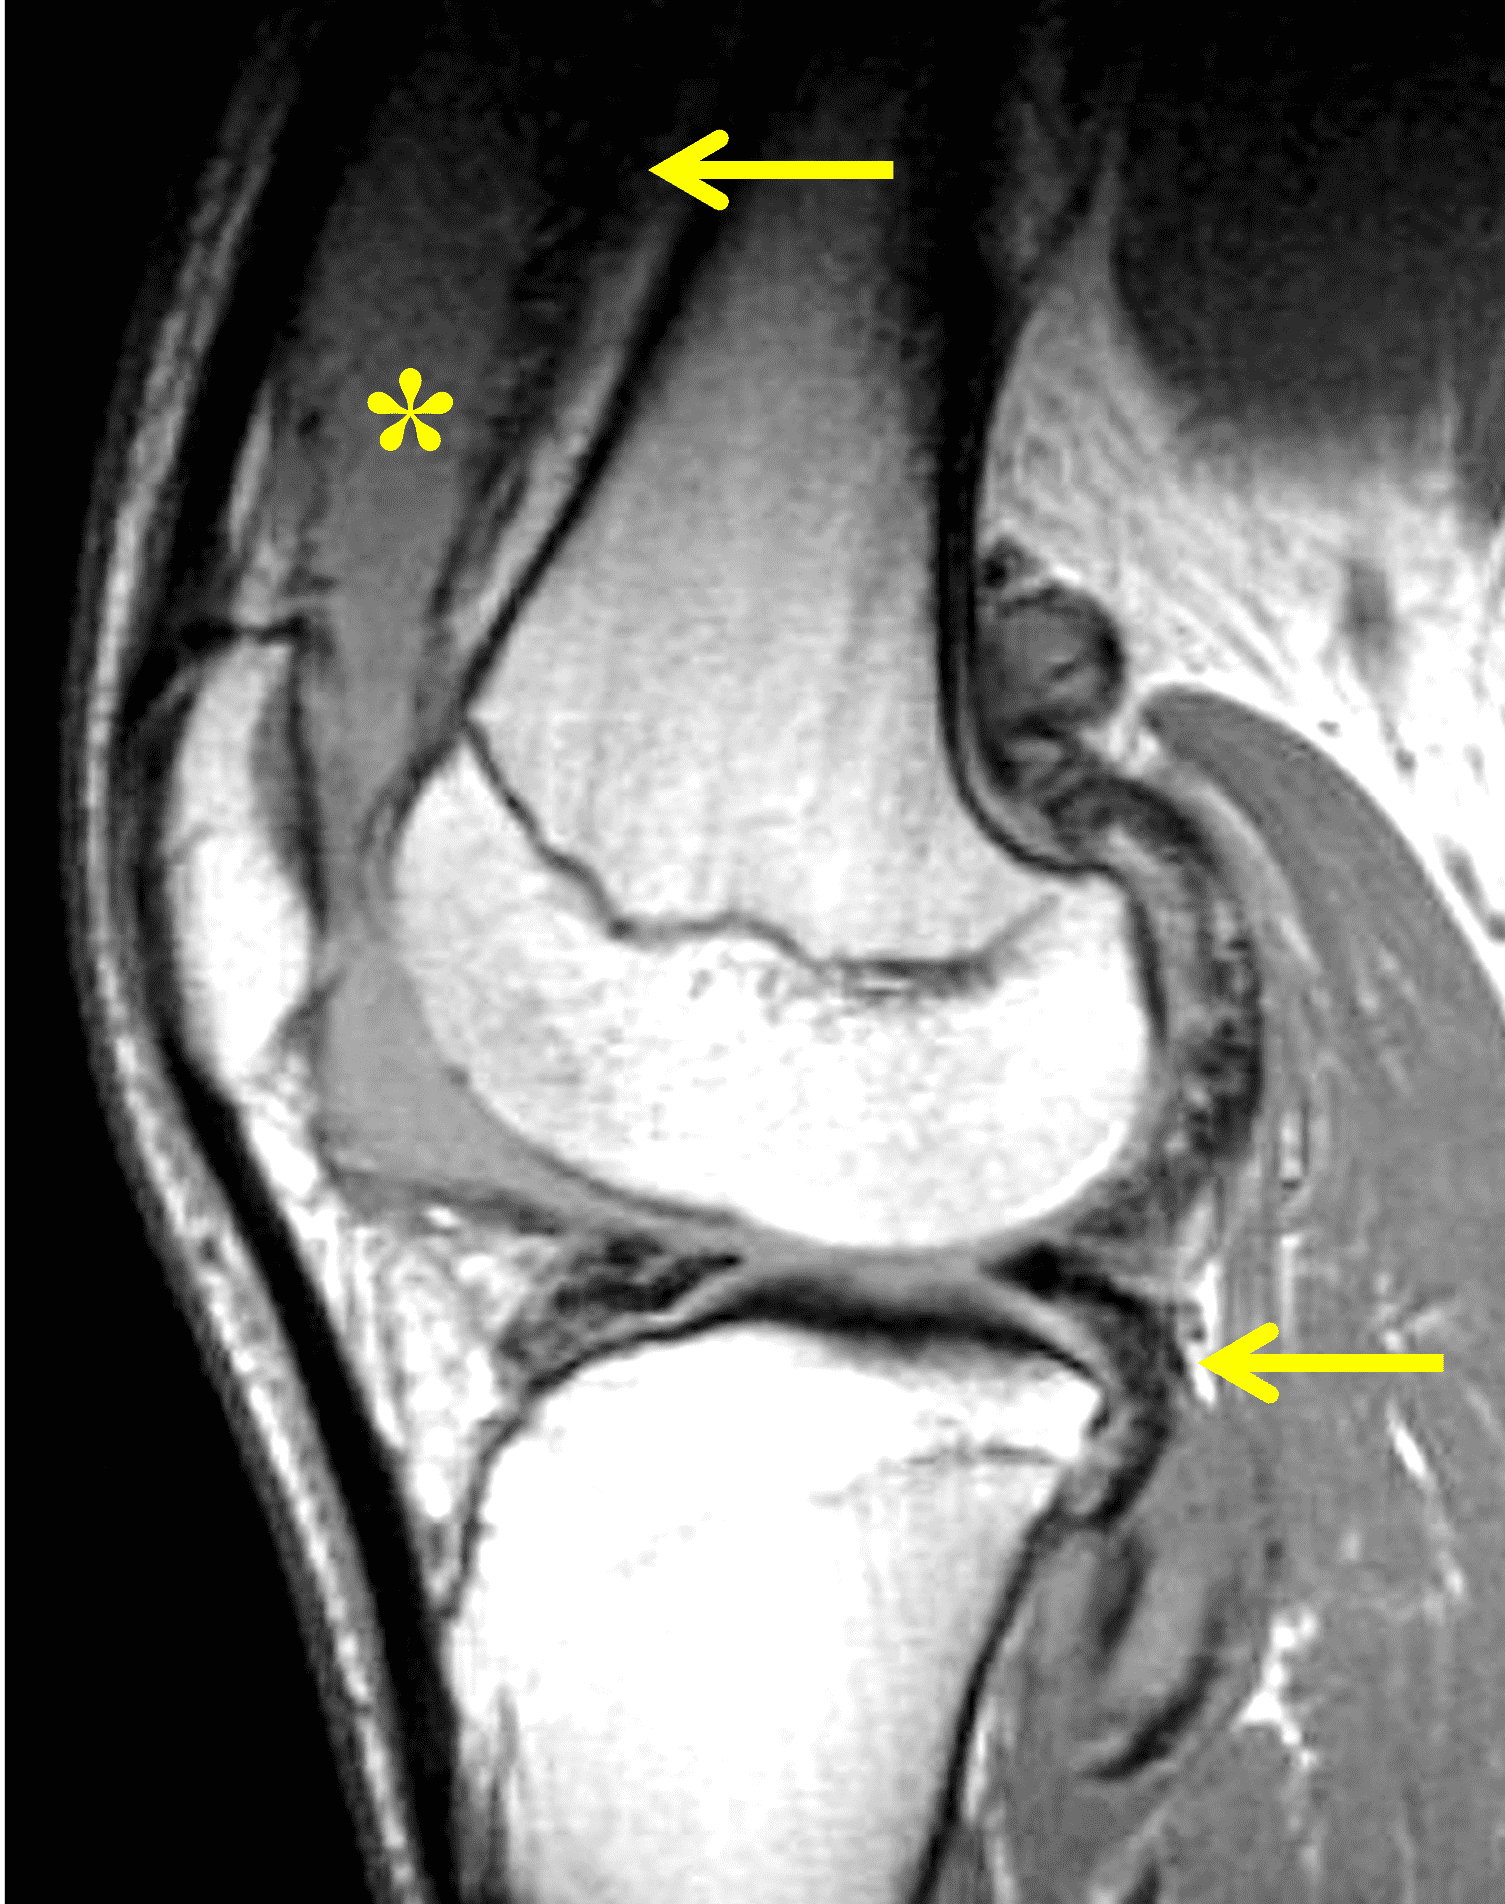

Figure 2: (2A) The coronal image shows a large effusion and severe hypertrophic synovitis (asterisks) in the knee. (2B) On the sagittal image the hypertrophic synovium (asterisks) involves the suprapatellar and infrapatellar recesses as well as the anterior and posterior intercondylar notch. A reactive lymph node (arrow) is present in the popliteal fossa. (2C) The axial image demonstrates myositis (arrows) involving the popliteus and peroneus longus muscles. Note the preserved articular cartilage, lack of erosions, and the absence of subcutaneous or marrow edema.

The causative spirochete invades the synovium, triggering a host inflammatory response that leads to synovial hypertrophy and inflammation, resulting in the characteristic clinical symptoms and imaging findings associated with Lyme arthritis.2 Common MR findings associated with Lyme arthritis include synovitis, joint effusion, popliteal lymphadenopathy, and myositis predominantly involving the popliteus (Figure 4).2,3,9 In contrast to acute septic arthritis due to more common bacteria, subcutaneous edema, marrow edema, erosions, and osteomyelitis are uncommon (Figure 4C).

Figure 4: Lyme arthritis. Fat-suppressed, fluid-sensitive images. (4A) Transverse image shows severe proliferative synovitis in the anterior and posterior joint recesses (arrows). Note the lack of surrounding subcutaneous edema. (4B) In addition to synovitis, the sagittal image shows multiple reactive lymph nodes (red arrows) and popliteal myositis (white arrow). (4C) Coronal image also shows patchy non-joint centered marrow edema in the distal femur and proximal tibia (asterisks), which is uncommon in Lyme disease compared to acute septic arthritis.